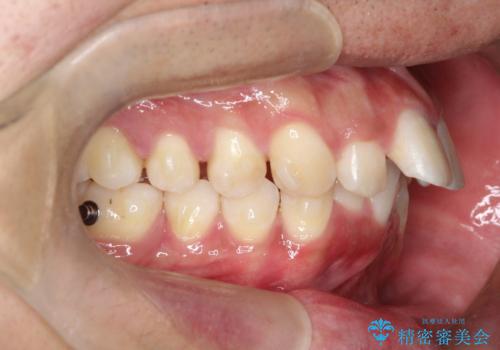

インビザラインによる出っ歯の矯正

- 出っ歯と下の歯のガタガタを主訴に来院されました。

上の奥歯を後方に移動させて、スペースを作り前歯を内側に引っ込める計画としました。

インビザラインによるマウスピース矯正で治療をすることとしました。

インビザラインをしっかり使用していただいたので、スムーズに治療をおえることができました。